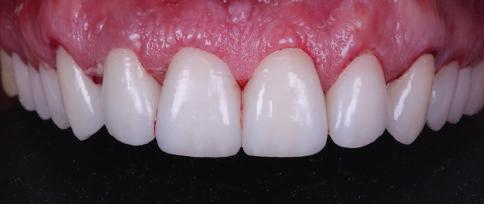

9Dental Tribune Bulgarian Edition / октомври 2022 г. След лечението За авторите: Д-р Манол Ивчев е създател на COLDY DENT Functional Atelier, завършва дентална медицина във ФДМ, София. Шест години е стажант в ортодонтска практика. Интересите му са изцяло насочени към функционалната дентална медицина. Посещава курсовете на Доусън и Льо Гал. Преминава редица обучения, акредитирани от Института на Славичек във Виена – VieSID. Впоследствие става най-младият инструктор във VieSID. Придобива права да преподава философията на проф. Рудолф Славичек в България. В практиката си се придържа към протоколите на Славичек за функционално лече ние и диагностика, тъй като те са насочени към комплексно лечение. Завършва всички нива за морфология на зъбите и моделаж при Janos Mako. Повишава знанията си по функционална ортодонтия чрез индивидуален курс в Румъния. Д-р Ивчев е и сертифициран зъболекар по лингвална ортодонтия от Катедрата по ортодонтия от Университета по стоматология в Тегу, Южна Корея. Сертифициран е и за лечение на ортодонтски аномалии чрез миофункционални апарати, а също и за ортодонтия, подпомагана от миниимпланти, отново от Университета по стоматология в Южна Корея. Завършва индивидуално обучение по функционална ортодонтия в Университета по дентална медицина в Богота, Колумбия, както и индивидуално обучение по функционална ортодонтия и физиотерапия по про токола на Mariano Rocabado. Има завършено индивидуално обучение по функционална зъботехника и функционален Wax-Up клас I,II и III. Завършва курс за Digital Smile Design и Skin Concept в Люксембург при Christian Coachman, Florin Cofar, Paulo Kano, Josef Kunkela, Livio Yoshinagа. Зт. Leandro Gambogi, Бразилия, завършва зъботехника през 1999 г. Експерт и пионер в дигиталната диагностика. Лектор и инструктор на курсове в областта на дигиталното протезиране. Понастоящем е главен изпълнителен директор и зъботехник в DENTALE DIGITAL LAB. В периода януари 2005 г. – декември 2006 г. завършва бизнес управление и администрация в Methodist University Center Izabela Hendrix. Съавтор на книгата Odontologia Digital: Desafiando os Limites, глава 5: „Дигитално включване във времето. Технология CAD/CAM“. Преминал множество обучения при световноизвестни кли ницисти. Фиг. 51 Фиг. 54 Фиг. 57 Фиг. 58 Фиг. 63 Фиг. 64 Фиг. 65 Фиг. 59 Фиг. 61 Фиг. 62 Фиг. 60 Фиг. 55 Фиг. 56 Фиг. 52 Фиг. 53 Фиг. 66

планта бе поставена временна коронка (фиг. 10 и 11), докато бъде изготвена окончателна та. Бе постигнат отличен кра ен резултат. Меките тъка ни около импланта напълно заздравяха, което доприне се за перфектната хармония между бяла и розова естетика (фиг. 12–15).